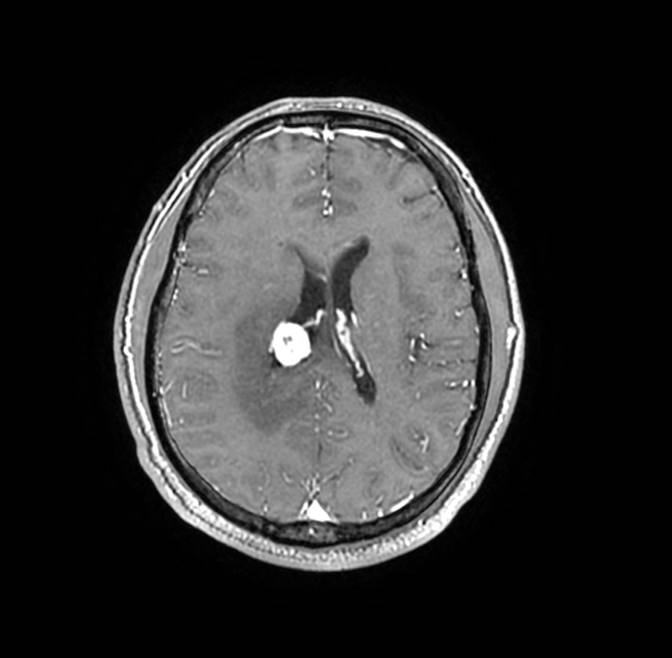

磁共振影像圖

圖4

MR診斷:右側(cè)側(cè)腦室三角區(qū)及側(cè)腦室旁占位,考慮惡性腫瘤可能,間變型腦膜瘤?轉(zhuǎn)移瘤?